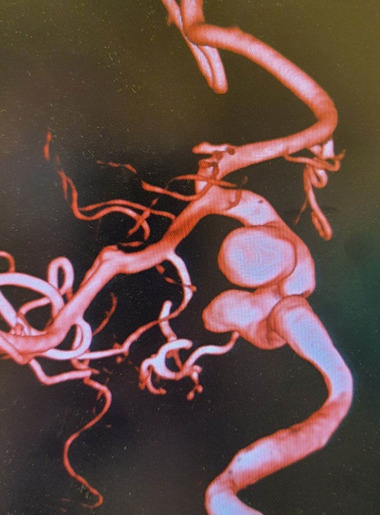

脑动脉瘤,也被称为脑动脉瘤,是母体动脉的生长。根据其形状,动脉瘤可分为囊状动脉瘤和非囊状动脉瘤。多种因素与多发性脑动脉瘤有关,但最常见的是动脉高血压。在脑动脉瘤的治疗中,像线圈栓塞这样的血管内技术基本上已经取代了手术夹闭。由于分流器的出现,脑动脉瘤的治疗发生了革命性的变化。它们现在用于治疗对标准治疗无反应的复杂动脉瘤,以及以前用标准手术或基于线圈的血管内手术治疗的未破裂病变。由于分流术并发症少,恢复率高,已被证明是一种比其他方法更成功的治疗动脉瘤的方法。我们讨论的情况下,病人谁到达头痛和随后被诊断为许多动脉瘤的左颈内动脉。血流分流支架植入用于栓塞患者现有的动脉瘤,随后作为术后需要进行双重抗血小板治疗(替格瑞洛和血栓ASS)。尽管我们的病人有大动脉瘤和小动脉瘤,但治疗后没有并发症。

Brain aneurysms, also known as cerebral aneurysms, are the growths of the parent artery. Based on their shape, aneurysms can be categorized as saccular or non-saccular. Several factors have been linked to multiple brain aneurysms but the most prevalent is arterial hypertension. In the treatment of cerebral aneurysms, endovascular techniques like coil embolization have essentially taken the place of surgical clipping. Brain aneurysm treatment has undergone a revolutionary change owing to flow diverters. They are now used for complex aneurysms that are unresponsive to standard therapies, in addition to unruptured lesions that were previously treated with standard surgical or coil-based endovascular procedures. Flow diversion has shown to be a more successful treatment for aneurysms than other approaches due to its reduced complication and high recovery rate. We discuss the case of a patient who arrived with headache and was subsequently diagnosed with numerous aneurysms of the left internal carotid artery. Flow diverter stenting was employed to thrombose our patient's existing aneurysms, followed by dual antiplatelet therapy (Ticagrelor and Thrombo ASS) as a post-procedural need. Despite the fact that our patient had both large and minor aneurysms impacting challenging locations, there were no complications after treatment.